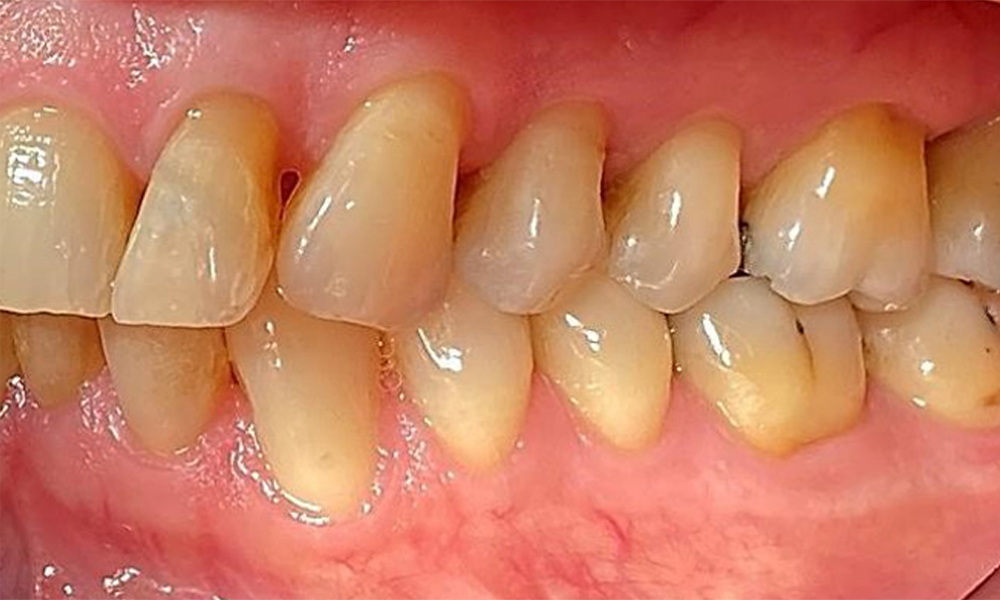

Зъбни резултати

Пациентът има пълно съзъбие с 28 зъба, което включва амалгамни и композитни пломби в областта на моларите и премоларите. На зъб 14 има видима клинична маргинална празнина. Зъб 27 има адекватна златна инкрустация. Налице са и генерализирани атриции и абразии. (фиг. 2, фиг. 3, фиг. 4, фиг. 5, фиг. 6)

Пародонтални резултати

Пациентът е с пародонтит II стадий, степен В (5). Клиничните дълбочини на сондиране от 1 до 3 mm са във физиологичния диапазон. Локализирани дълбочини на сондиране от 5 mm са наблюдавани медиопалатинално на 17 и 27. Налице са генерализирани рецесии от 1 до 3 mm с частична загуба на интердентални папили (фиг. 2, фиг. 3, фиг. 4)